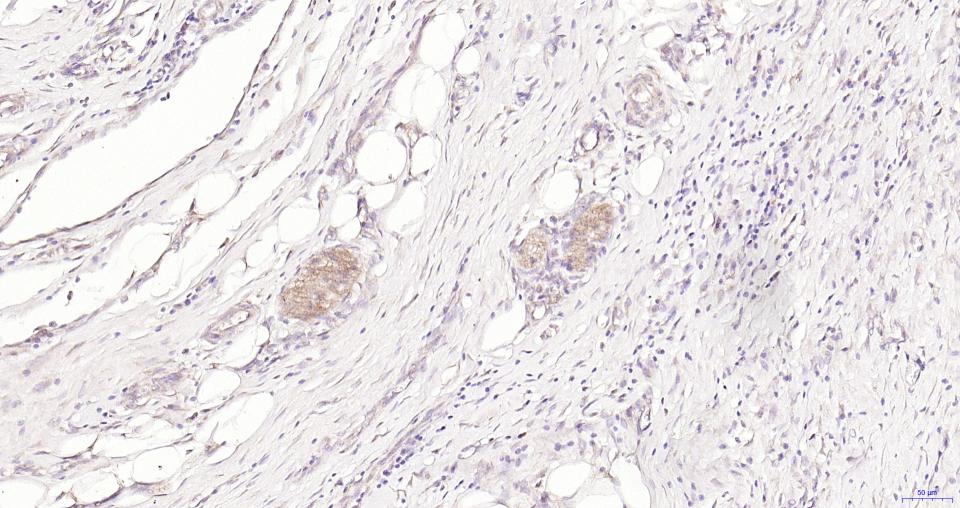

细胞粘附蛋白(Call Adhesion Protein) 神经元标志物 NCAM-1为神经细胞粘附分子,主要分布于神经组织,神经—肌肉接头,神经—内分泌腺和某些内分泌腺以及大多数神经外胚层来源的细胞、组织和肿瘤中。 NCAM 1主要用于视网膜母细胞瘤、髓母细胞瘤、星形细胞瘤、神经母细胞瘤等肿瘤方面的研究。CD56(神经细胞黏附分子,NCAM)表达于大部分神经外胚层来源的细胞系、组织和肿瘤如视网膜母细胞瘤、成神经管细胞瘤、星形细胞瘤以及成神经细胞瘤。它也表达于一些中胚层来源的肿瘤如横纹肌肉瘤。NK细胞以及NK细胞淋巴瘤为阳性。CD56被认为是NK细胞肿瘤的重要标志物。该抗体识别分子量为180,145和125kDa亚型。